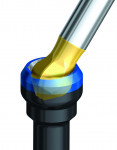

Cementation process must be controlled, and the dentist should be directed as to how much cement to use. This can be easily achieved by providing a copy polyvinyl siloxane (PVS) abutment that allows extra cement to be extruded out of the crown extra-orally before it is seated18 (Figure 7 and Figure 8).